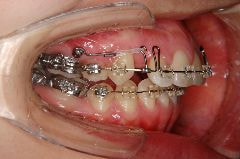

歯科矯正用アンカースクリューの使用例

例2)

➡︎